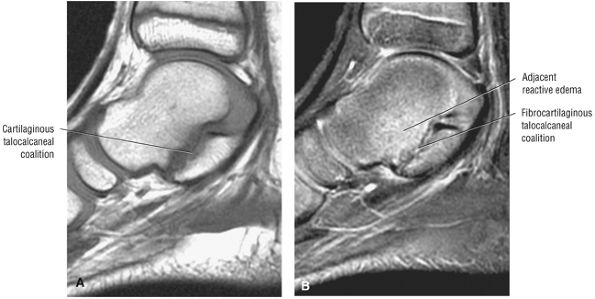

Thickening (Fig. 5.180) or absence of the ligament in acute injury

-

Subacute to chronic residual thickening in a healed and scarred ligament (Fig. 5.181)

Chronic instability associated with attenuated or hypoplastic ligament with sharper, more defined ligament margins